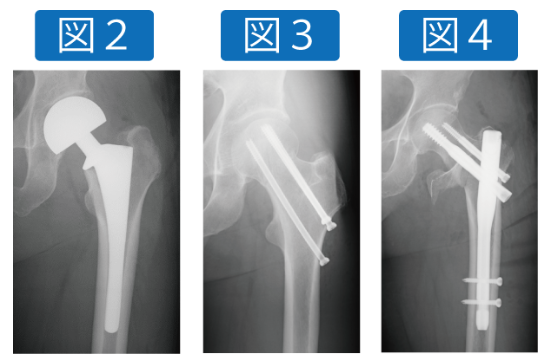

手術の方法は骨折の型によりますが、ずれの大きい頚部骨折は人工骨頭置換術(図2)、ずれの少ない頚部骨折はスクリュー固定(図3)、転子部や転子下骨折は髄内釘型の金具を使って手術することがほとんどです(図4)。しっかりと手術をして手術翌日から歩行練習等を始めることで、最近のデータでは入院は約1ヶ月程度となっております。